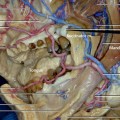

Fig. 7.1. The midfacial region. The lower lateral portion of the orbicularis oculi muscle has been reflected.

Innervation to the lower orbicularis oculi muscle and zygomaticus major muscle are shown. The zygomaticus major muscle is innervated by the zygomatic branches and also from the zygomaticobuccal branches (see Fig. 7.5) in its lower part of the muscle. The lower orbicularis muscle is innervated from its inferolateral side by one or two zygomatic branches and temporal branches.

The zygomaticofacial nerve (shown in Fig. 7.1 with blue sheet under it) is a sensory nerve, which supplies the small region of the cheek, and it is divided from the zygomatic nerve in the orbit.

The transverse facial artery, which originates from the superficial temporal artery within the parotid gland, courses anteriorly beneath the masseteric fascia above the parotid duct.